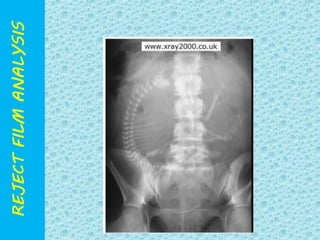

POSITIONING ERROR

UNDER EXPOSED

X-RAY FILM

OVER

EXPOSED X-RAY

FILM

PATIENT POSITONING ERROR